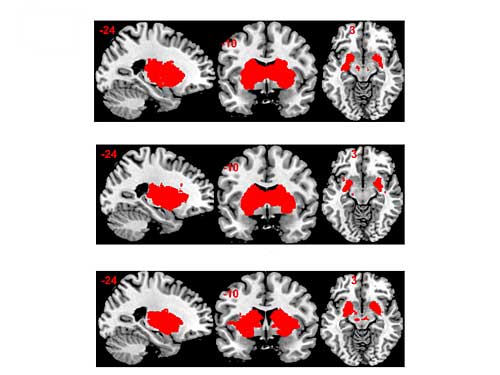

Ergebnis der Pilotstudie: Fruktose ist im Vergleich zu Glukose weniger gut in der Lage, Sättigungsgefühle hervorzurufen und die Belohnungssysteme im Gehirn zu stimulieren. Die Auswertung der MRIs zeigte nämlich, dass sich die beiden Zuckerarten in der Netzwerkaktivierung innerhalb des limbischen Systems mit Hippocampus und Amygdala deutlich unterscheiden - in jener Hirnregion, die Emotionen und Triebe reguliert. Zudem stiegen die Sättigungshormone im Blut nach dem Fruktosekonsum kaum bis wenig an - im Gegensatz zur Glukose, die ein starkes Signal hervorrief. Das subjektive Sättigungsgefühl war tendenziell ebenfalls weniger von der Einnahme von Fruktose beeinflusst.

Bildunterschrift: Im Belohnungssystem im Gehirn sind die Unterschiede zwischen dem Placebo (oben) und den zwei Zuckerarten Glukose (Mitte) und Fruktose (unten) deutlich zu erkennen, wie das MRI-Bild zeigt.